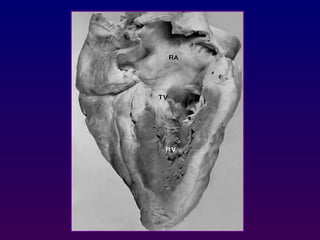

Right ventricular inflow and outflow

Inferomedial angulation from the parasternal long-axis

position is performed to obtain the "right ventricular

inflow" view which includes the right atrium,

coronary sinus, septal and anterior leaflets of the

tricuspid valve and basal right ventricle

Right ventricular inflowand outflow Inferomedial angulation from the parasternal long-axis position is performed to obtain the "right ventricular inflow" view which includes the right atrium, coronary sinus, septal and anterior leaflets of the tricuspid valve and basal right ventricle •Superior angulation of the probe permits depiction of the right ventricular outflow tract, including the pulmonic valve and main pulmonary artery. PVTV RA